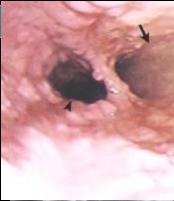

Orifice de ulcere dans

oesophagite a CMV . Image fibroscopie de oesophage

|